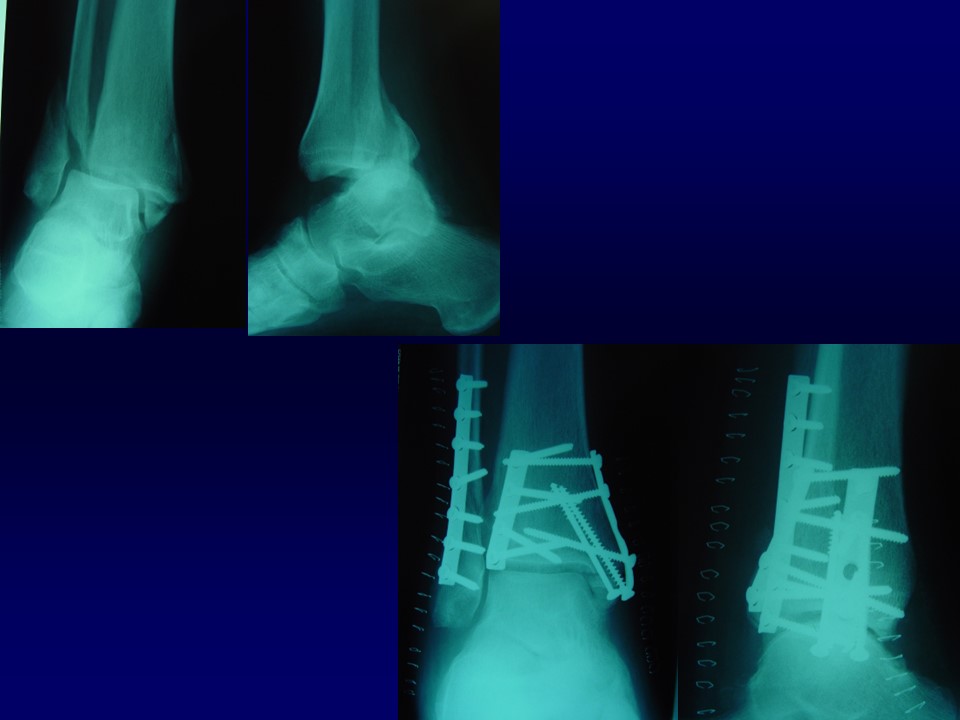

踝关节骨折的治疗PPT

Ramsey and Hamilton: 1 毫米的外移, 胫距关节接触面积将减少42%